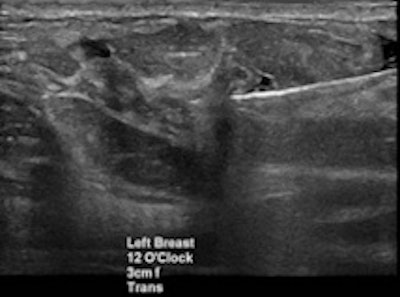

Targeted ultrasound for the palpable lump in the left breast showed vague hypoechoic area at 12 o’clock which was core biopsied under ultrasound guidance (left). Pathology of left breast ultrasound core biopsy was benign, however at multidisciplinary breast care conference, pathology result was found to be discordant with imaging findings on ultrasound, and further evaluation with breast MRI (right) showed an irregular enhancing left breast mass in the upper, central to inner breast which was confirmed to be invasive ductal carcinoma on excisional biopsy."Diagnosis doesn't stop with the biopsy; it's even more important to correlate the biopsy results with the imaging finding," she said.